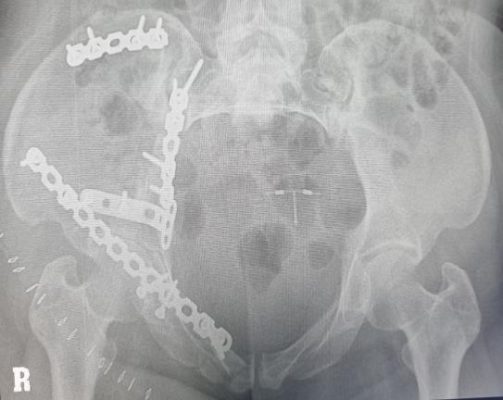

- Chụp Xquang khung chậu ngày thứ 7 sau mổ, kết quả đã nắn chỉnh khung chậu và ổ cối về vị trí giải phẫu. Chân phải bệnh nhân trong quá trình hồi phục, đang tập phục hồi chức năng, tập đi lại, vết mổ khô, không có biến chứng không có các biến chứng như tổn thương thần kinh, nhiểm khuẩn sớm…, cắt chỉ ra viện ngày thứ 10 sau mổ.

Hình 5: Xquang sau mổ